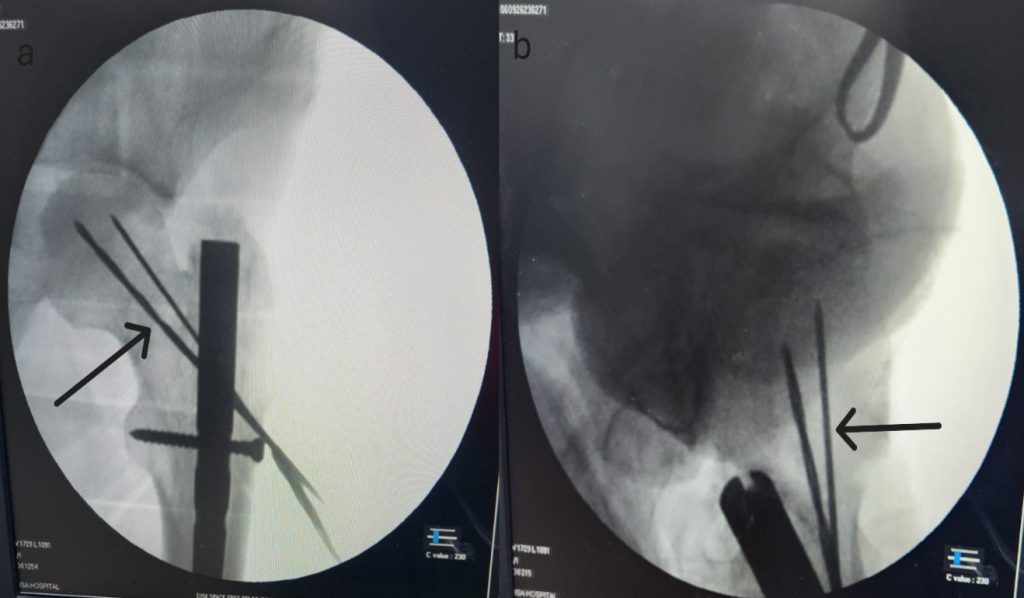

To resolve this issue, we replaced the threaded guide wire with a 2.5 mm Kirschner wire in our case, which allowed us to create a path away from the nail towards the femoral head without breaking upon contact with the nail or proximal locking screw. After reducing the femoral neck fracture, we observed space under the C-arm, with the anterior space visible in the lateral view and the inferior space in the AP view. This space allowed us to insert two K-wires, which were then checked under the C-arm (Fig. 2a-b). Shows two K-wires passed posterior to the nail and missing the nail, with the arrow marked. Afterward, the 2.5 mm Kirschner wire was removed, and the 2.0 mm threaded guide wire was inserted into the path created by the Kirschner wire. Two partially threaded 6.5 mm cannulated compression screws were then inserted, achieving fracture compression and reduction without disturbing the in situ nail, as shown in the post op image in (Fig. 3a-c) it shows post-op image neck of femur fracture in AP (3a, 3b) and lateral images (3c), with well-reduced neck of femur with CCS screw with femur interlocking nail in situ. This approach helped reduce operative time, blood loss, and fracture displacement while minimizing intraoperative and post-operative complications.

Figure 2: Intra-op image neck of femur fracture with the femur interlocking implant in situ in anteroposterior (a) and lateral images (b), arrow showing K-wire passed without disturbing the nail.